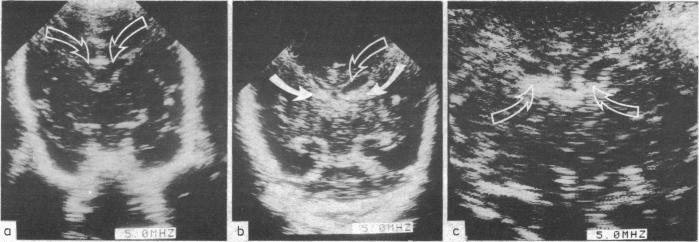

Forty four babies, of less than 32 weeks' gestation, were either randomly given 25 mg/kg vitamin E (DL-alpha-tocopherol acetate) intramuscularly after birth (day 0) and on days 1, 2, and 3 or served as controls. Frequent real time ultrasound examinations of the brain were made in each baby during the first week and less frequently thereafter. In babies under 32 weeks' gestation the incidence of intraventricular haemorrhage was lower in supplemented babies (18.8%) compared with the controls (56.3%). On days 0, 1, 2, and 3 median plasma vitamin E concentrations in babies without haemorrhage and in those with subependymal haemorrhage only were similar. Babies with intraventricular haemorrhage had lower median concentrations on day 1 (p less than 0.002) and day 2 (p less than 0.05) compared with those with subependymal haemorrhage and lower concentrations on day 0 (p less than 0.02) and day 1 (p less than 0.05) compared with those without haemorrhage. These findings suggest that in premature babies vitamin E, an antioxidant, protects endothelial cell membranes from oxidative damage and disruption and limits the magnitude of haemorrhage and its spread from the subependyma into the ventricles.

44名孕周小于32周的婴儿,出生后(第0天)及第1、2、3天被随机分为两组,一组肌肉注射25mg/kg维生素E(DL-α-生育酚醋酸酯),另一组作为对照组。在第一周内对每个婴儿进行频繁的脑实时超声检查,之后检查频率降低。在孕周小于32周的婴儿中,补充维生素E的婴儿脑室内出血发生率(18.8%)低于对照组(56.3%)。在第0、1、2、3天,无出血的婴儿和仅发生室管膜下出血的婴儿血浆维生素E浓度中位数相似。与室管膜下出血的婴儿相比,脑室内出血的婴儿在第1天(p<0.002)和第2天(p<0.05)的血浆维生素E浓度中位数较低;与无出血的婴儿相比,脑室内出血的婴儿在第0天(p<0.02)和第1天(p<0.05)的血浆维生素E浓度较低。这些发现表明,对于早产儿,抗氧化剂维生素E可保护内皮细胞膜免受氧化损伤和破坏,并限制出血的程度及其从室管膜下向脑室的扩散。